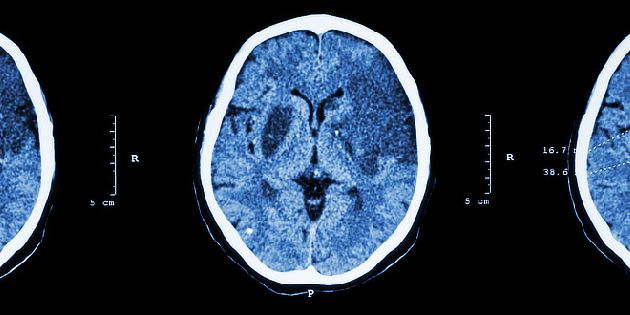

Mozkové aneurysma se diagnostikuje prostřednictvím zobrazovacích metod. Existuje-li podezření na dosud neprasklé aneurysma, používá se většinou MRI nebo angiografie. Pokud naopak existuje podezření na prasklé aneurysma, je možné provést přesnou diagnózu pomocí CT a případně (pokud CT nález je negativní, ale pacient vykazuje stále příznaky ruptury aneurysmatu) lumbální punkci (z páteřního kanálu se odebere malé množství mozkomíšního moku a pokud je v něm přítomna krev, podezření na krvácení do mozku je potvrzeno).